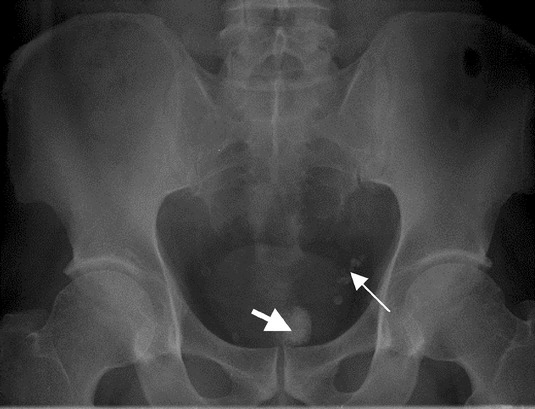

이후 그녀는 화장실 청소용 솔과 집게로 돈 뭉치를 꺼내려 했지만 출혈이 심해져 병원으로 옮겨졌다.

그녀의 몸에서 꺼낸 돈 뭉치는 절도 증거로 채택돼 경찰이 보관중이다.